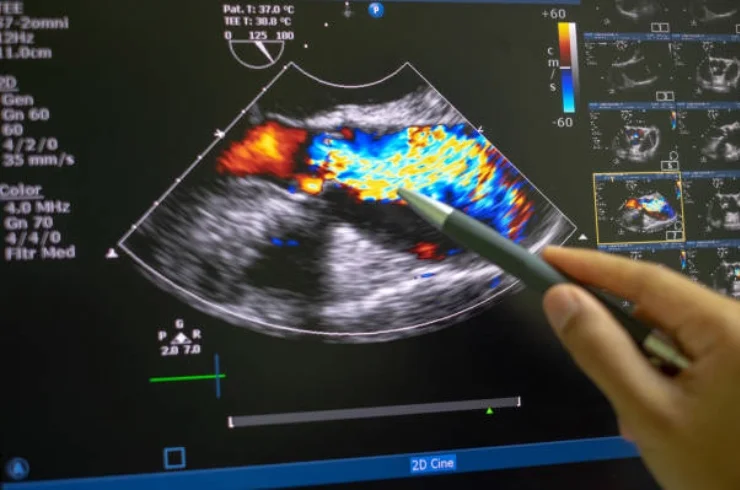

Cardiac ultrasound (echocardiogram) to assess heart function and detect abnormalities in heart structure and activity.

Advanced Doppler ultrasound to assess blood flow, identify blockages, and evaluate vascular conditions.